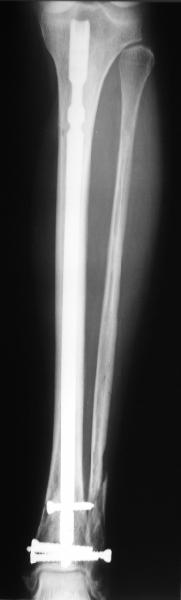

A typical case is attached, also an image with intra-op reduction obtained by a small wire distractor, in the moment of insertion a Poller wire in AP direction. Fixation by a SIGN nail. Despite the fibula was not fixed healing was obtained with the unchanged alignment.

At least both the ankle mortise and tibial alignment look acceptable, don't they?

I am just trying to illustrate that prevention of 1)tibial valgus and 2)loss of reduction can be provided without fibular plating. Small changes of conventional nailing techniques allow to maintain reduction of the tibia reliably without adjunctive fibular stabilization.

In delayed cases acute length restoration performed only in the tibia may leave the fibula shortened thus change the mortise. So it is reasonable to restore length of both bones simultaneously by distractor and fix the fibula not with open reduction and plating but just by a single perQ screw. Example attached.